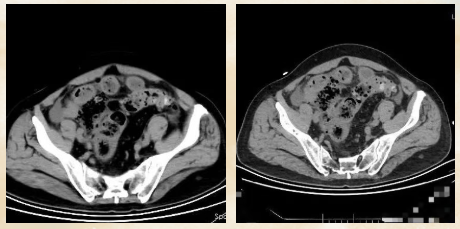

70岁的赵大叔长期便秘,但总觉得“上了年纪都这样”从未进行系统检查。直到在家中排便困难,出现腹痛并加剧才来到青岛西海岸新区中医医院肛肠科就医。 检查结果令人震惊: CT显示腹腔有游离气体,高度怀疑肠穿孔。

急诊手术中,医生发现他的结肠部位已发生恶性肿瘤并导致了穿孔。经过紧急肿瘤切除和肠道造口手术,在重症监护室恢复近一周时间才逐渐病情稳定。但后续仍需进行化疗。

医生:长期便秘并出现腹痛加重、腹胀、消瘦等症状,一定要警惕肠道肿瘤的可能性。肠穿孔是急症,延误可危及生命!